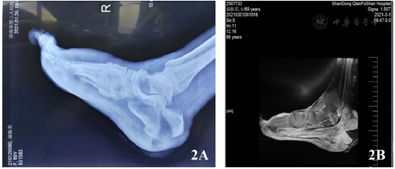

入院查体:双下肢等长,等粗;左外踝尖可见1.5cm×1.5cm大小创面,创面黑色痂皮覆盖,创缘周围有少量渗出;左足踇趾内侧可见5cm×4cm大小创面,创面深达深筋膜,有脓性渗出物;左足第4、5趾可见皮肤破溃,创缘周围皮肤颜色发红,有少量渗出;左足跟内侧见2cm×1cm大小结痂,创面干燥,无明显渗出;足跟外侧见5cm×5cm大小结痂,创缘有渗出;右小腿远段后侧见5cm×4cm大小创面,创面结痂,创缘有少量渗出;右足踇趾畸形,右足跟肿胀明显,可见4cm×2cm、1cm×1cm大小创面,呈空腔,深达跟骨(图1),肉芽组织不新鲜,有大量渗出。双侧股动脉、腘动脉、胫后动脉搏动(+);双侧足背动脉搏动(-);双下肢各关节活动正常,无感觉活动障碍。双足感觉明显减退。

2021年1月26日,外院X线检查:右足跟骨骨折